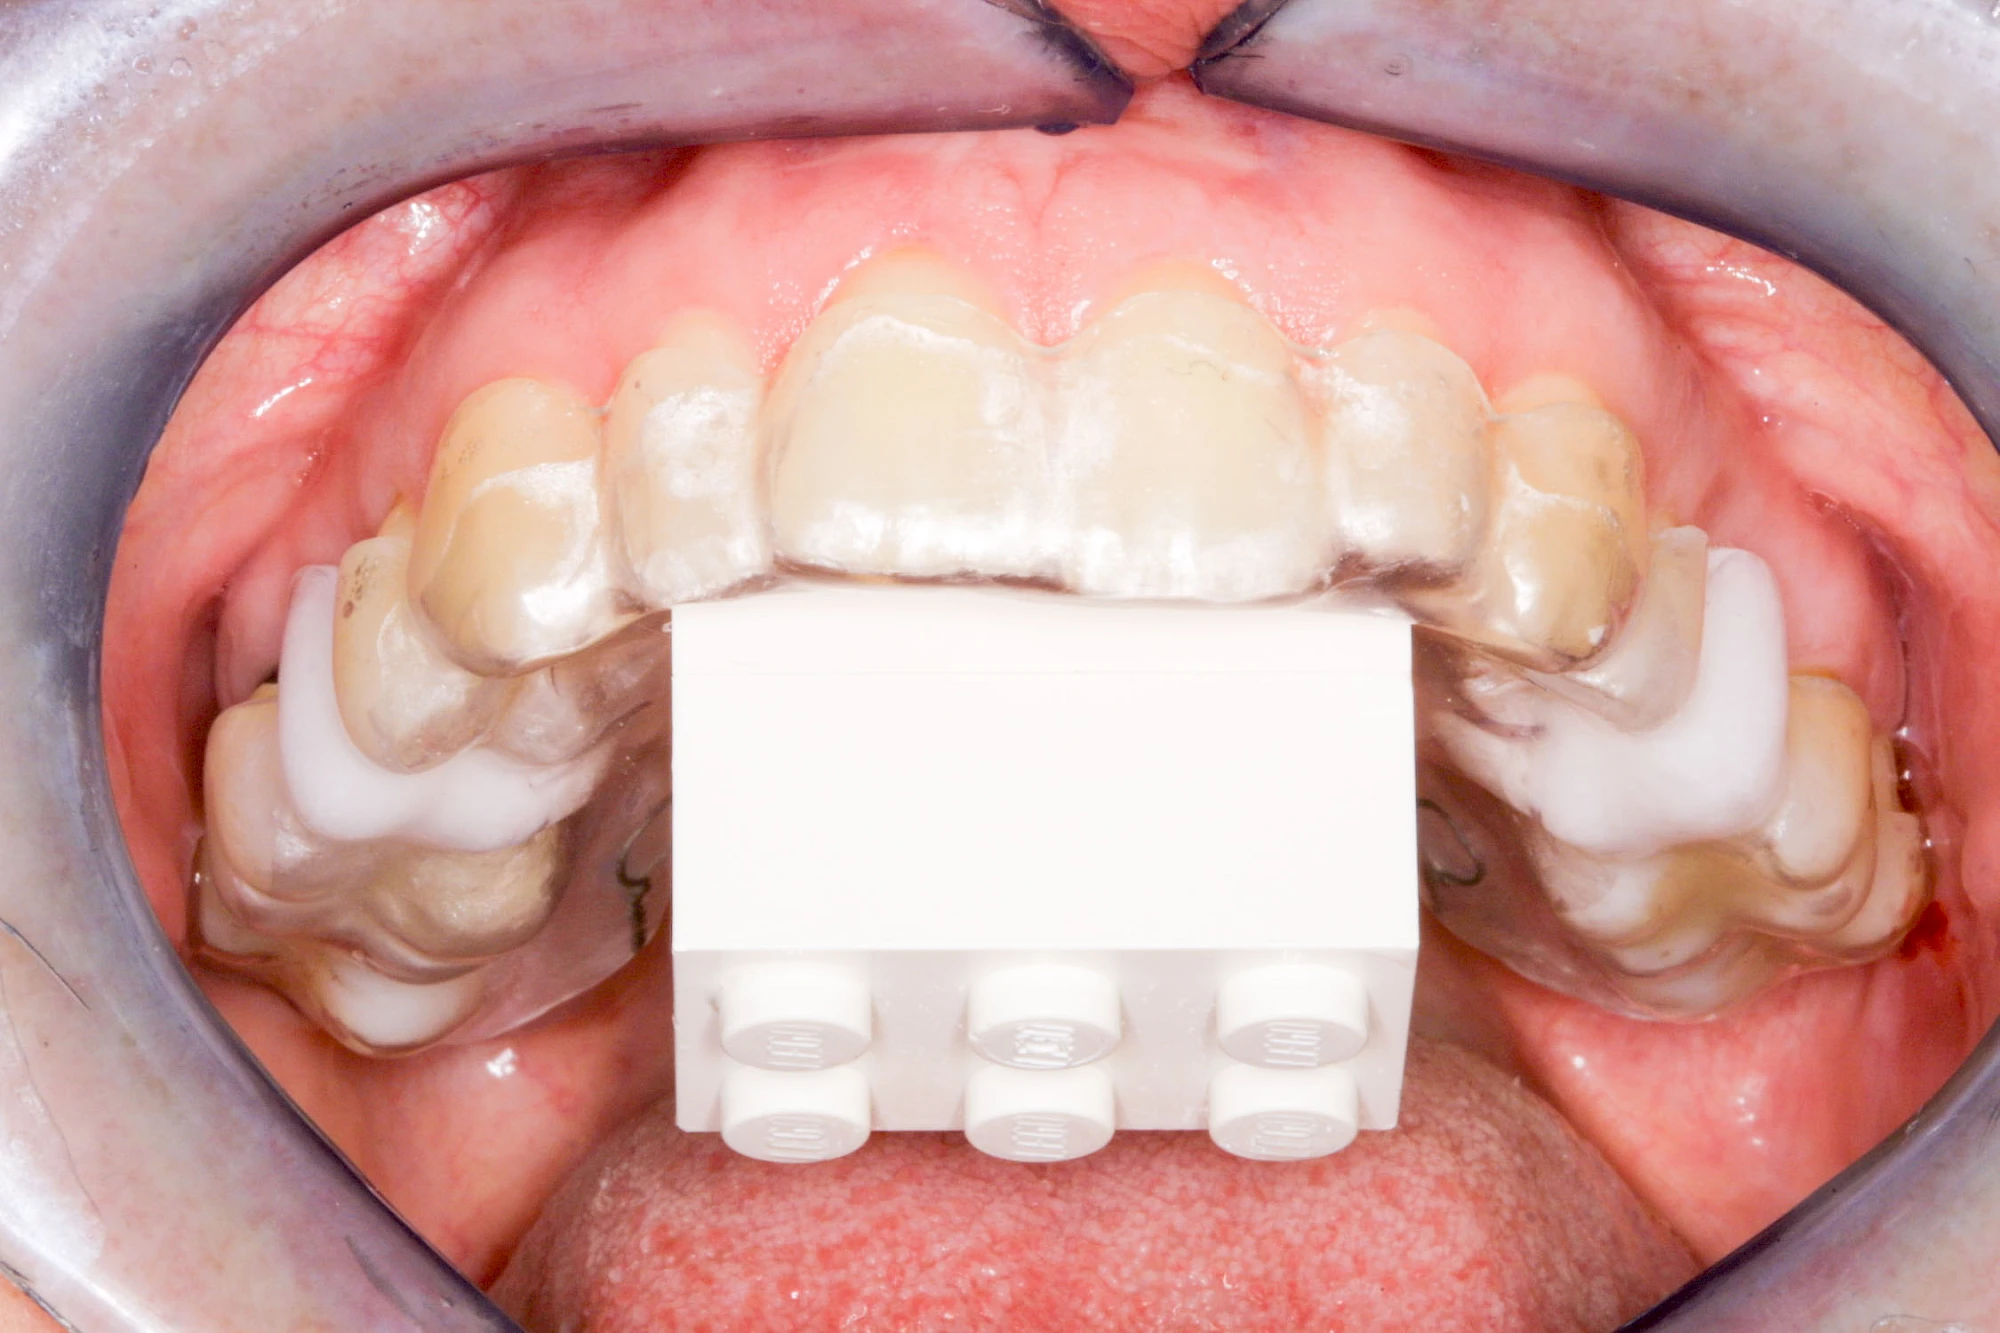

Implantatplanung

Damit Implantate an der richtigen Stelle im Kieferknochen platziert werden könen, gibt es heute vielfältige Möglichkeiten der Planung. In vielen Situationen kann die Erfahrung des Zahnarztes ausreichend sein.

Nicht selten ist jedoch auch eine technisch aufwändigere Vermessung im Vorfeld sinnvoll, z. B.:

In diesen Fällen kann die Planung mittels verschieden aufwendiger Röntgen-Techniken (Übersichtsaufnahme, DVT) ggf. unter Zuhilfenahme speziell angefertigter Planungsschablonen sinnvoll sein.